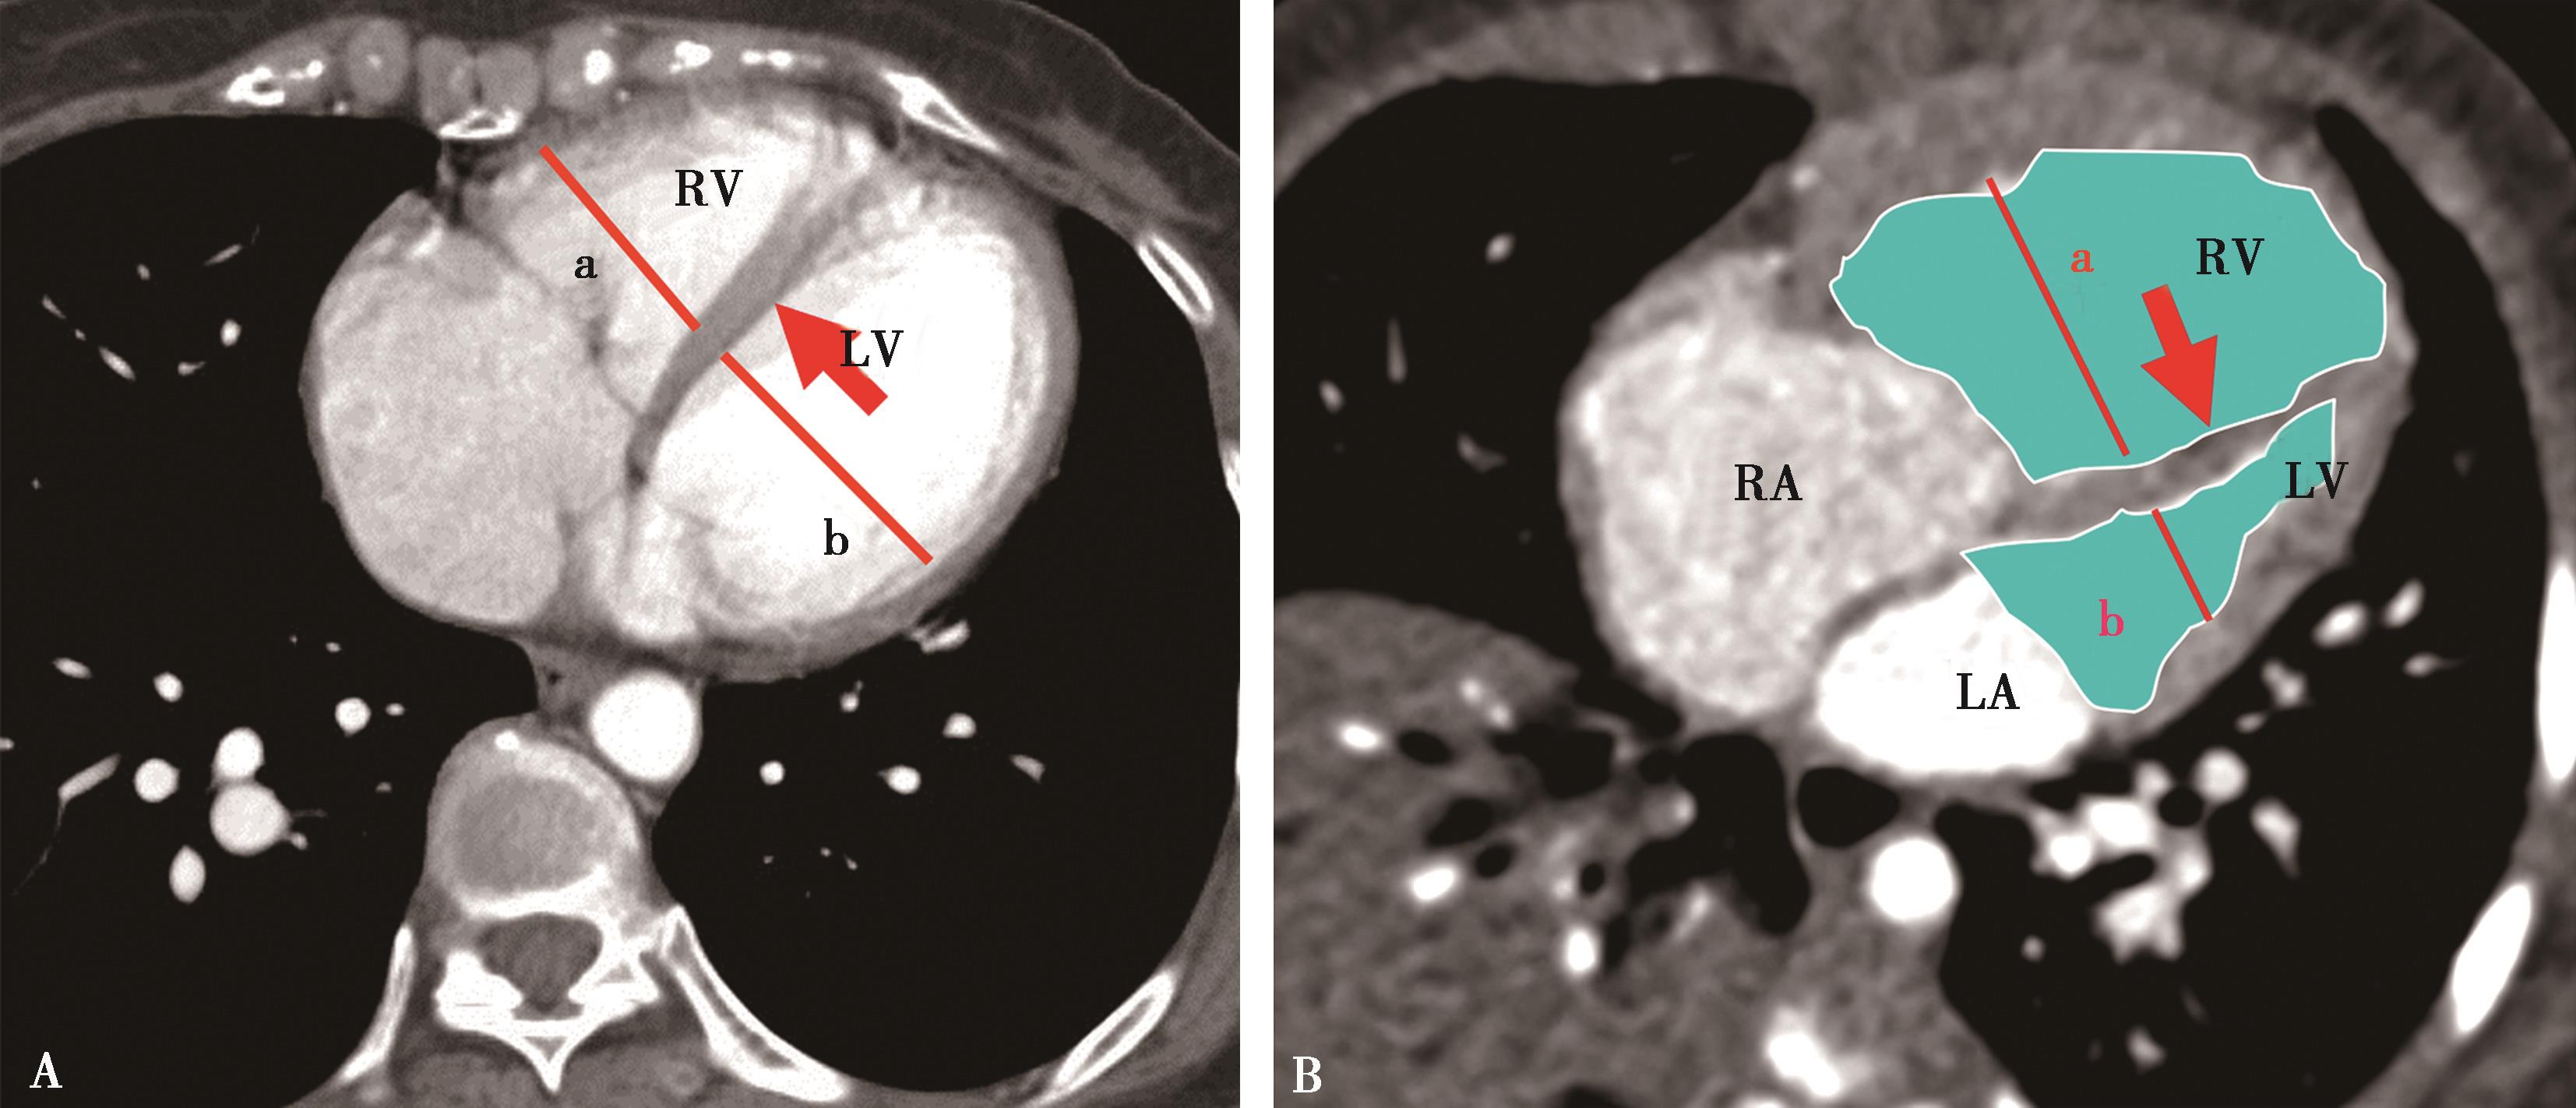

1.右心室增大

横断像心室最大层面测量左右心室最大横径(图8-3-10),正常心脏右心室横径:左心室横径<1,(a∶b<1),室间隔居中(红色↑)。右心室增大,右心室横径:左心室横径>1,(a∶b>1),室间隔凸向左心室(红色↑)。

2.右心室增大心脏顺钟向转位

横断像心室间隔与纵轴夹角可以反映右心室增大;由于右心室增大,心脏顺钟向转位,室间隔与纵轴夹角增大(图8-3-11)。

图8-3-10 横断图像

A.正常心脏,a∶b<1; B.右心室增大,a∶b>1

图8-3-11 横断图像

A.正常心脏;B.右心室增大,顺钟向转位,室间隔与纵轴夹角增大(↑)